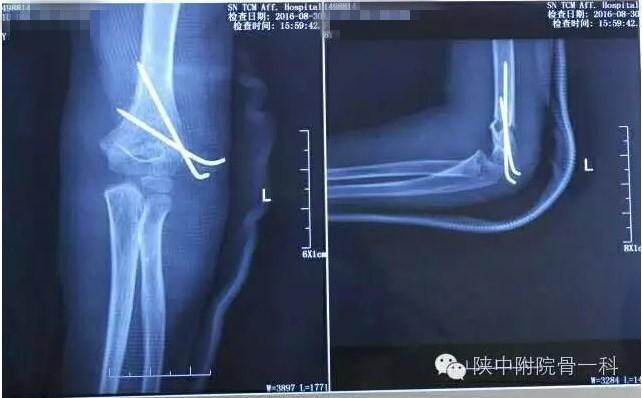

肱骨髁上骨折闭合复位手术记录,小儿肱骨髁上骨折手术恢复的概率 病案一:患儿XX,女,8岁,摔伤后左肘关节疼痛伴活动受限3小时入院。

肱骨髁上骨折闭合复位手术记录,小儿肱骨髁上骨折手术恢复的概率 诊断:Gartland Ⅱ型骨折

急诊行闭合手法复位克氏针内固定,术后X线片(下图)

肱骨髁上骨折闭合复位手术记录,小儿肱骨髁上骨折手术恢复的概率

术后长臂石膏维持屈肘中立位固定(下图)